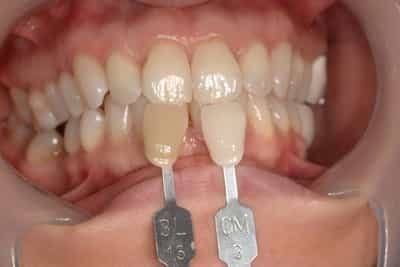

Eclaircissement Dentaire ou Blanchiment

L’éclaircissement dentaire est une technique consistant à rendre aux dents une couleur plus harmonieuse, plus en adéquation avec l’image que le patient veut donner de lui. Le blanc des yeux est une référence. A l’échelle du visage, la blancheur de la sclérotique de l’oeil (blanc des yeux) fait ressortir la couleur jaune des dents. Pour une meilleure harmonie, il faut aligner ces deux couleurs. Si les dents sont moins lumineuses, l’éclaircissement va améliorer l’apparence. Après éclaircissement, cette différence s’atténuera et donnera une harmonie du visage.

Dans d’autres cas, il s’agit d’une usure de l’émail. L’émail est responsable de la luminosité de la dent, et son usure a tendance à révéler la couleur de la dentine sous-jacente. Elle peut être marron, jaune, grise, orange… L’éclaircissement agit sur les colorations intrinsèques et extrinsèques, en surface et en profondeur.

Souvent, il sera plus judicieux de réaliser un éclaircissement avant un travail prothétique, ou des composites antérieurs, car les techniques d’éclaircissements ne sont pas actives sur les céramiques ou les composites.

On distingue deux types d’éclaircissement:

-le blanchiment externe : il concerne les dents vivantes et consiste à l’application d’un gel éclaircissant sur l’extérieur des surfaces dentaires. Cette technique de homebleaching nécessite obligatoirement l’accompagnement de votre dentiste. Il faut savoir gérer les éventuelles sensibilités pouvant apparaitre dans de rares cas. Le blanchiment doit être encadré dans son protocole et sur toute sa durée.